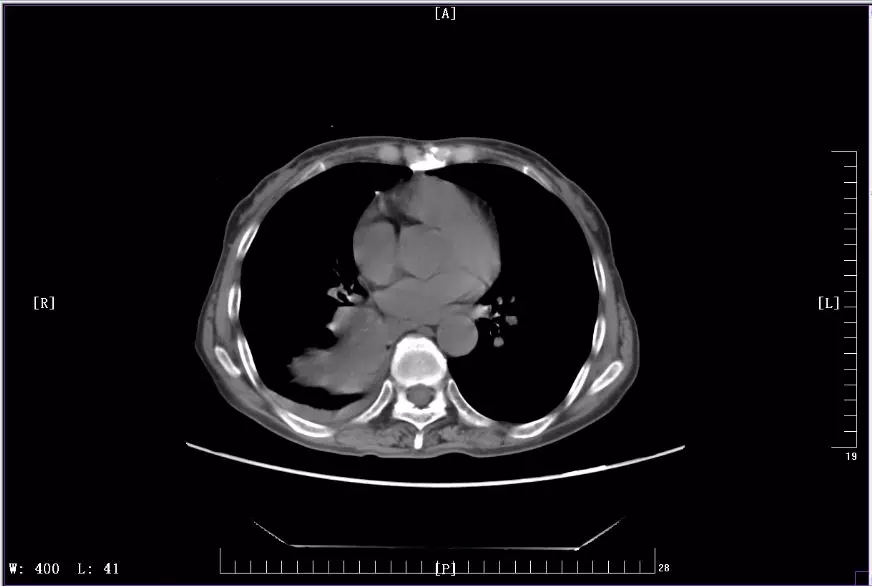

下图是徐丽参加KEYNOTE-407临床试验前后CT影像对比图:

2018年6月治疗中CT影像